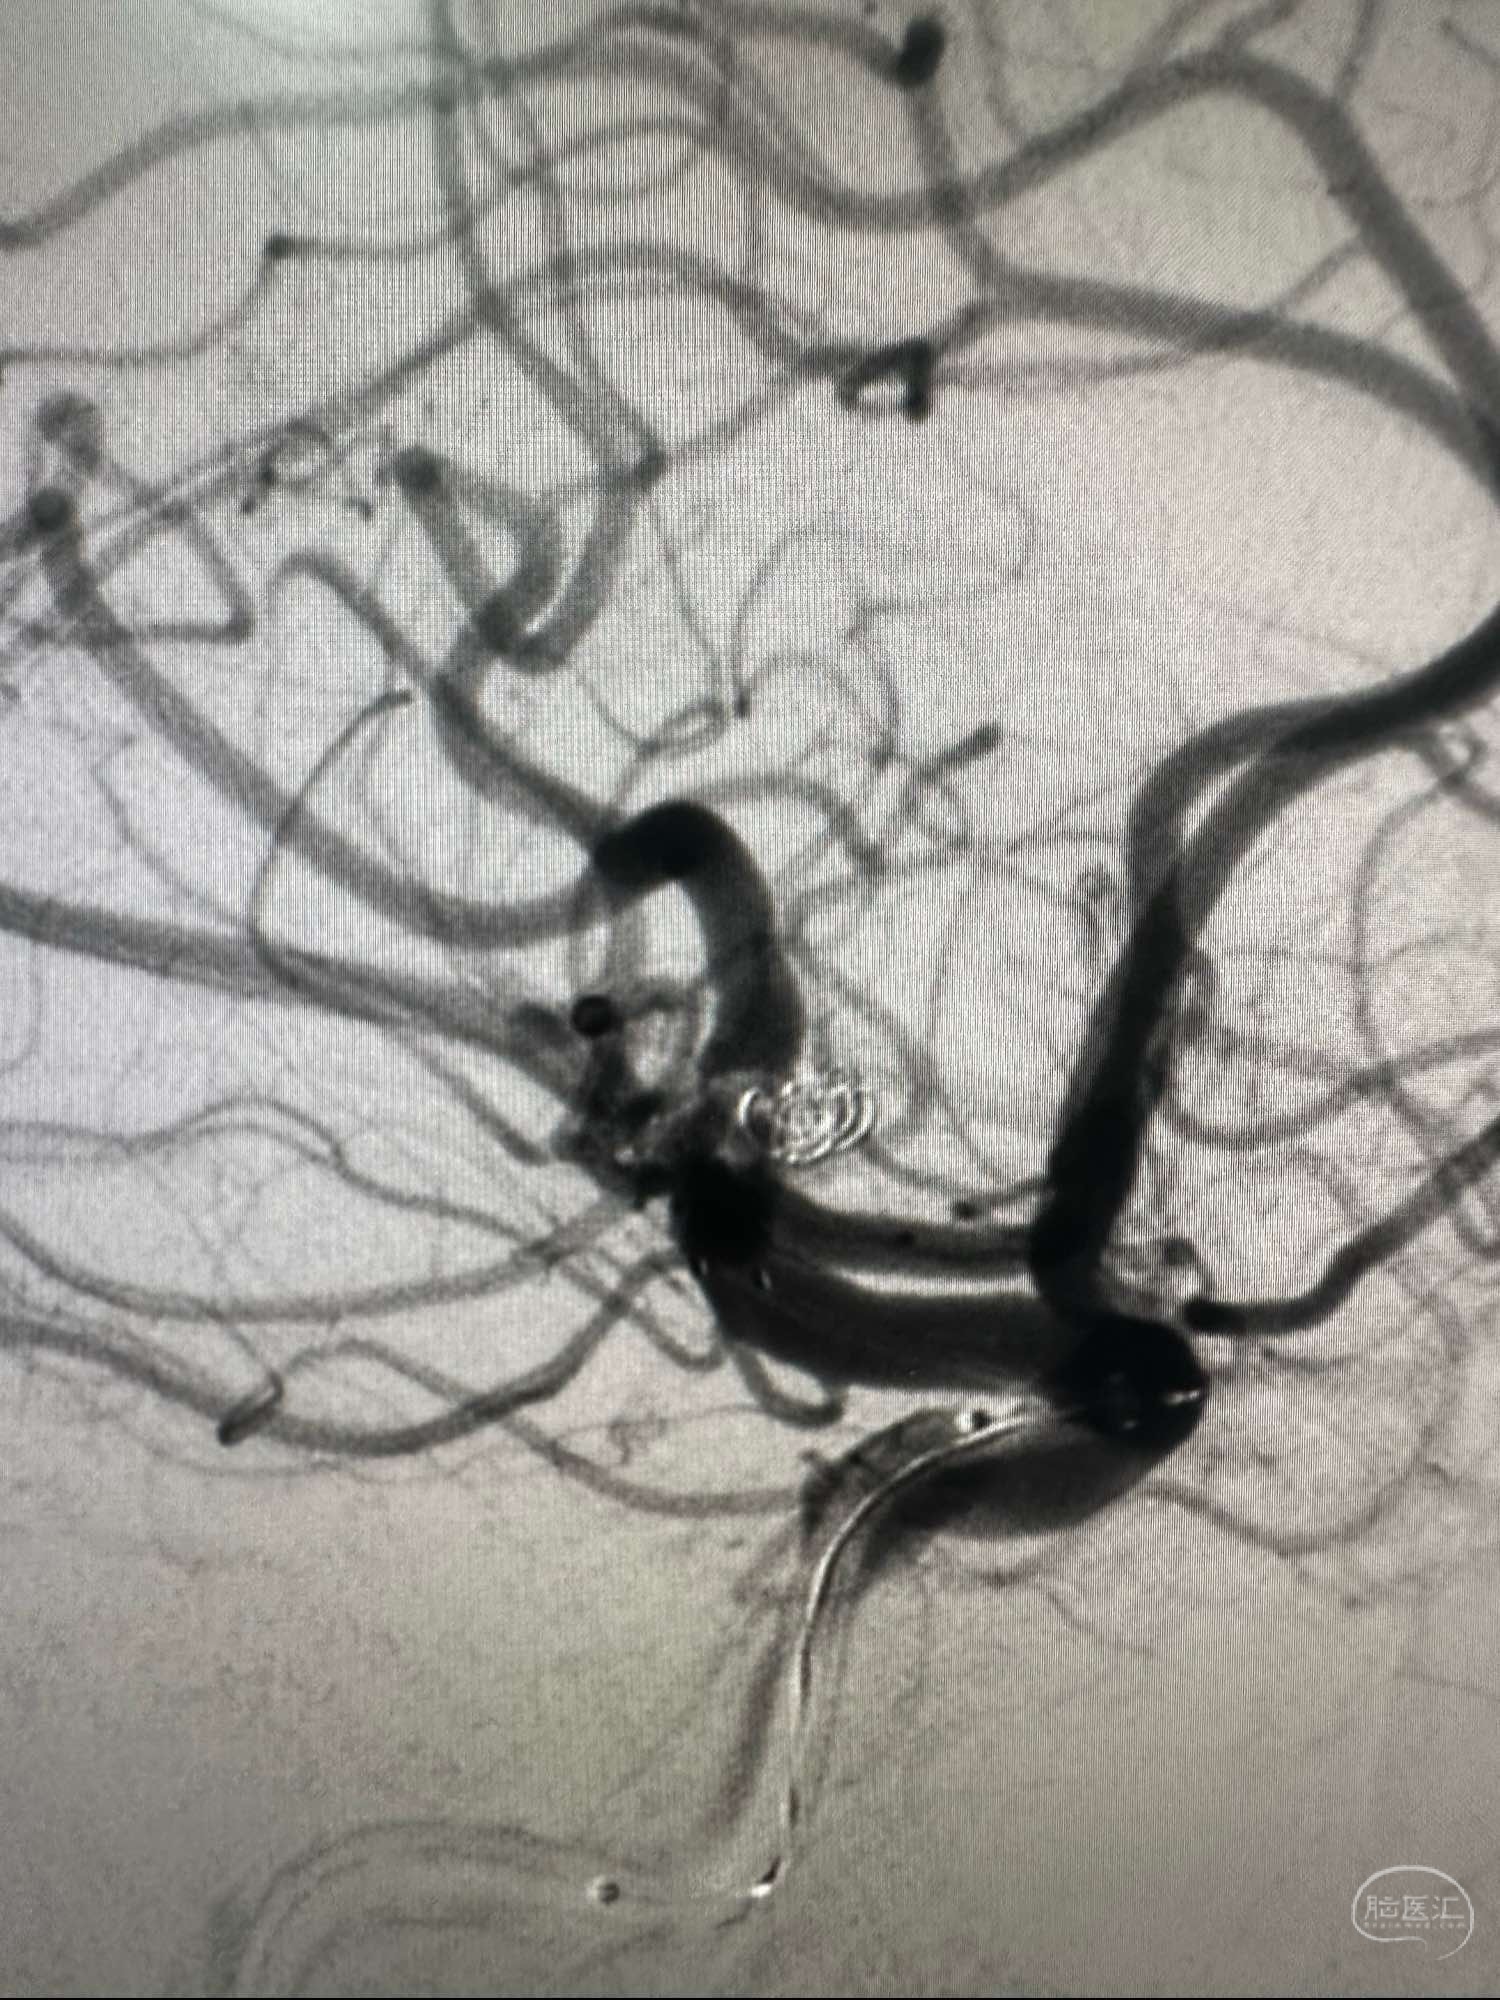

第一枚圈选择3*8的加奇的3D,出了几个襻后直接释放Atlas支架3*21

第一枚圈填塞后的形态,圈没有影响上干血流

第一枚圈的形态

后续再次填入2*4的加奇圈,另外一个角度造影见动脉瘤已经不显影

圈的形态